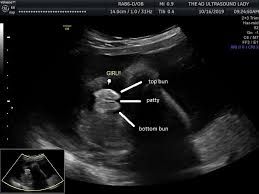

Изображение Изображение Как по мне это девочка

Olga D, вот я начиталась про 4 полосочки,то значит девочка....вроде они есть и хорошо просматриваются. Но смущает то что посередине

Татьяна, я на узи в 13.5 увидела почти такую же картину, но пол мне не сказали, я сделала анализ на определение пола, жду. Смущает вот эта длинная палочка посередине 😂

Алёна Юдина, вот и меня она смущает) узист сказала похоже на мальчика,но не точно